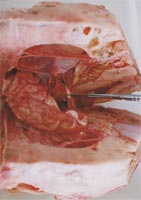

1 視神経を切断し,脳を取り出す.(写真4)

2 脳を横断面で切り離し(大脳,小脳,脳幹等の観察),一方をさらに縦断面で切る→皮質,髄質が色の違いで見事に観察できる.

写真4 メスで視神経を切断